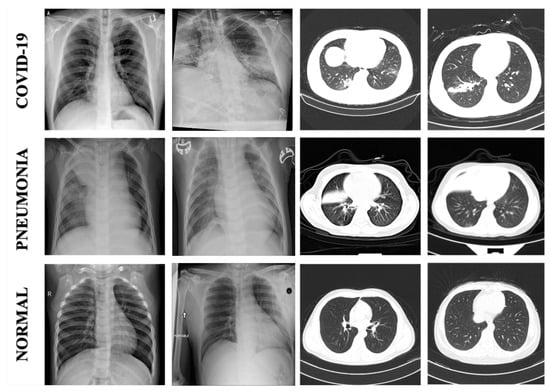

2.1. Data Sets